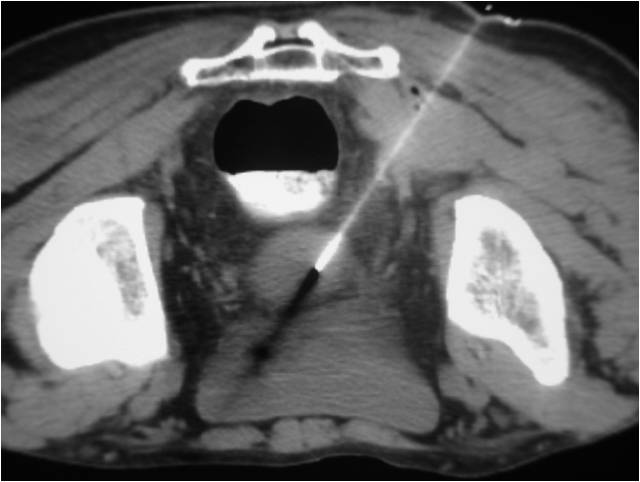

- Paracentisis of a deep pelvic abscess

- Successful catheter placement in a deep pelvic abscess